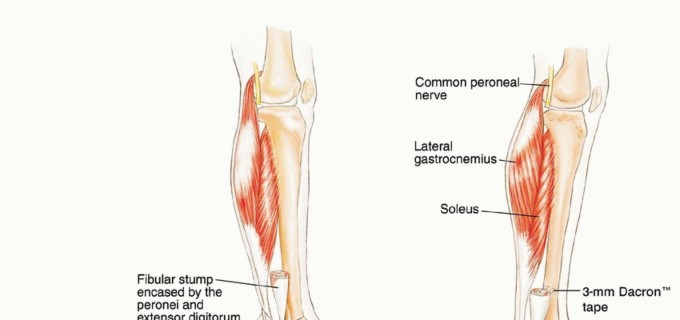

الشظية القريبة (Proximal Fibula): تُعد الشظية القريبة (الرأس والجزء العلوي من العظم) موقعًا رئيسيًا لالتصاق الرباط الجانبي الوحشي (LCL) ووتر العضلة ذات الرأسين الفخذية. هذه الروابط ضرورية لاستقرار مفصل الركبة من الناحية الجانبية. كما أن الرأس الشظوي يتصل بالظنبوب القريب ليشكل المفصل الظنبوبي الشظوي القريب. يمر العصب الشظوي الشائع (Common Peroneal Nerve) خلف رأس الشظية مباشرة، مما يجعله عرضة للإصابة أثناء الجراحة في هذه المنطقة.

جسم الشظية (Fibula Shaft): هو الجزء الطويل والرفيع من العظم، ويوفر نقاط ارتباط للعديد من عضلات الساق التي تتحكم في حركة الكاحل والقدم، مثل العضلات الشظوية (Peroneal Muscles) التي تقوم ببسط القدم للخارج (eversion).

الشظية البعيدة (Distal Fibula): تُعرف أيضًا بالنتوء الكاحلي الوحشي (Lateral Malleolus)، وتشكل جزءًا أساسيًا من مفصل الكاحل، حيث توفر الاستقرار الجانبي وتمنع الإفراط في حركة الكاحل. الأربطة التي تربط الشظية البعيدة بالظنبوب وعظام القدم ضرورية لوظيفة الكاحل الطبيعية.